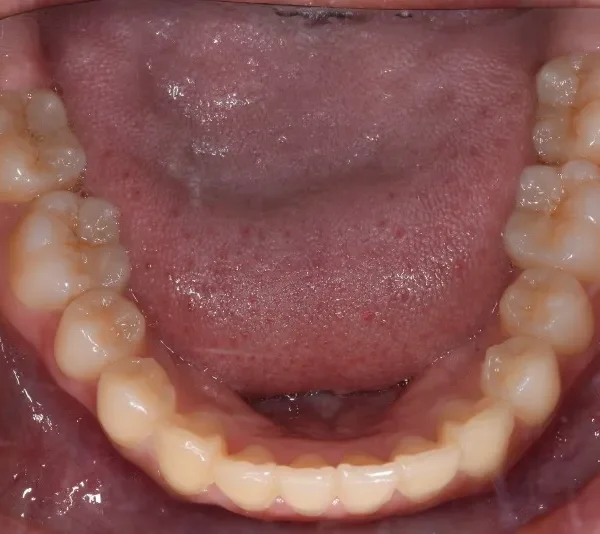

• 初診

上下がガタガタで犬歯の生えるすきまがありません。

このままだと犬歯の生えるスペースがありません。放っておくと犬歯が上の位置からはえ、牙のようになってしまいます。